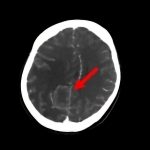

断層撮影

手術前2